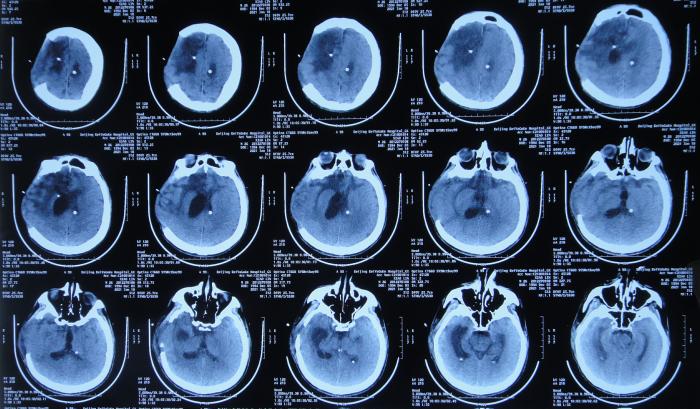

患者于2020年12月12日,在工作时意外从货车上摔下致头颅受伤,出现意识不清,送至河北省定兴县某医院,急诊查头颅CT示颅内血肿,中线有偏移( 图-1 ),给予开颅颅内血肿清除术+去骨瓣减压术,留置引流管,并行气管切开术;术后当天查头颅CT示开颅术后状态( 图-2 ),转入ICU病房。

图-1: 2020年12月12日头颅CT